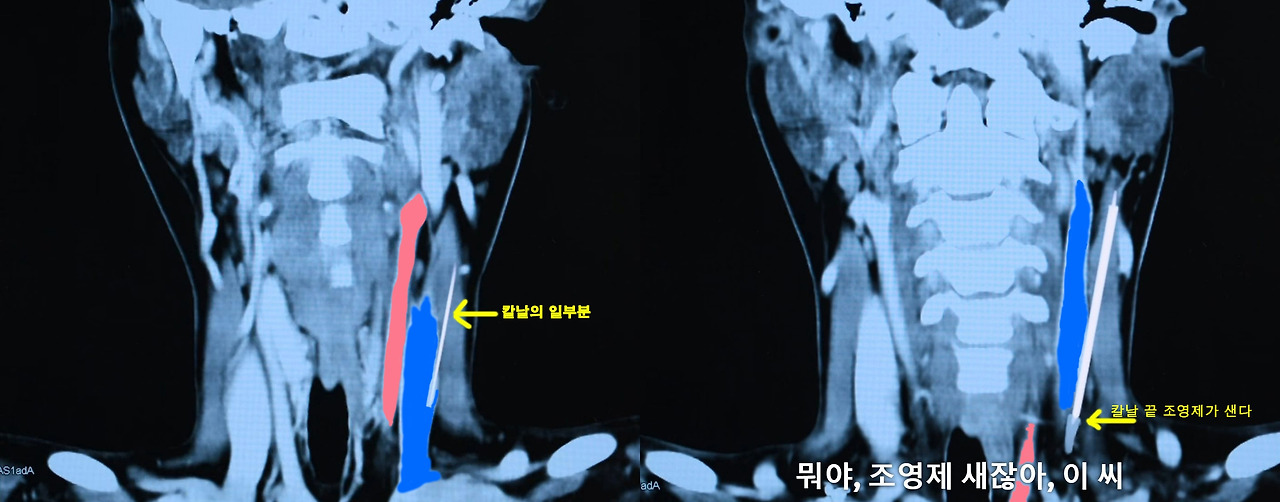

그런데, 드라마의 이 부분을 제가 자세하게 확대해서 살펴본 결과...

드라마에서 나온 CT 영상만 놓고 보았을 때는 환자의 경동맥 (Carotid Artery)이 아니라, 내경 정맥 (Internal Jugular Vein 일명 안주글라 정맥)이 손상되었다는 결론을 내릴 수 있었습니다.

드라마 CT 영상을 확대해서 살펴보면...

칼날이 가장 바깥쪽 혈관을 손상시키고 있고 조영제가 새는 부분도 가장 바깥쪽 혈관입니다.

그런데 해부학을 제대로 공부해 본 분들은 잘 아시겠지만, 사람 목에서 가장 바깥쪽에 위치한 혈관은 단연코 내경정맥입니다.

좀 더 보기 쉽게 하기 위해서 바깥쪽 혈관을 파란색으로 칠해 보았고, 좀 더 안쪽에 있는 경동맥은 빨간색으로 칠해 보았습니다.